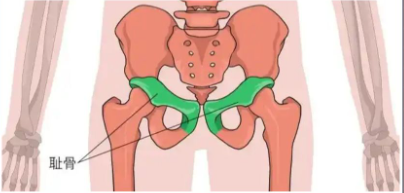

为了获得直观印象,先上一张图:这是骶髂关节,它的主要作用是稳定骨盆并缓冲上半身重量传递至下肢时的冲击力。

关于骶髂关节,再上一张图来说明一下耻骨的重要性。

女性耻骨位于髋骨前下部,由左右两块骨头组成,通过韧带和软骨连接在一起。耻骨在女性的身体中起着重要的支撑作用,是骨盆的重要组成部分。